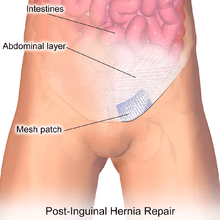

The most commonly performed inguinal hernia repair today is the Lichtenstein repair. A flat mesh is placed on top of the defect.[5]

It is a "tension-free" repair that does not put tension on muscles, contrary to Bassini and Shouldice suture repairs (but there are also tension-free suture repairs, like Desarda). It involves the placement of a mesh to strengthen the inguinal region. Patients typically go home within a few hours of surgery, often requiring no medication beyond paracetamol (Tylenol/acetaminophen). Patients are encouraged to walk as soon as possible postoperatively, and they can usually resume most normal activities within a week or two of the operation. Complications include chronic pain (varying from 10-50% depending on source), foreign-body sensation, stiffness, ischemic orchitis, testicular atrophy, dysejaculation, anejaculation or painful ejaculation in around 12%. They are often under-reported.[6][7][8][9] Recurrence rate is low, <2%.. In contrast to this however, benefits for patients with pre-existing erectile dysfunction or general sexual dysfunctions have been reported.[10]